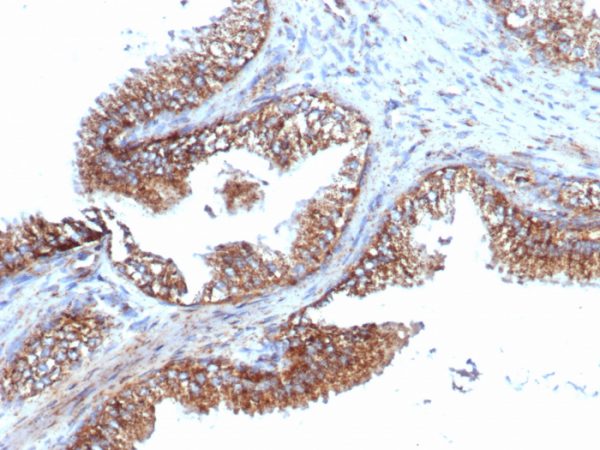

Formalin-fixed, paraffin-embedded human prostate carcinoma stained with PMEPA1 Recombinant Rabbit Monoclonal Antibody (PMEPA1/6421R).

PMEPA1 (prostate transmembrane protein, androgen induced 1 is a 287 amino acid single-pass membrane protein that contains WW-binding motifs and localizes to the cell membrane. Expressed at high levels in prostate, kidney and ovary, PMEPA1 interacts with NEDD4 and may play a role in regulating AR (androgen receptor) levels, specifically in prostate cells. Down regulation of PMEPA1 is observed in prostate tumors, suggesting that PMEPA1 may exhibit activity as a tumor suppressor. Overexpression of this protein may play a role in multiple types of cancer.